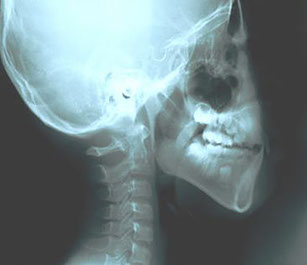

This is a boy who has adenoids caused by his snaggletooth and long-term oral breathing. After improving his oral breathing habit, his adenoids condition improved.

Adenoids - before and after

Before: throat inflammation due to oral respiration

Before using Patakara

Cephalogram before and after using Patakara

Solid lines: Before using Patakara

Dotted lines: After using Patakara for 20 months

After using for 20 months, changes in the cervical lines and facial bones can be seen clearly from the X-ray.